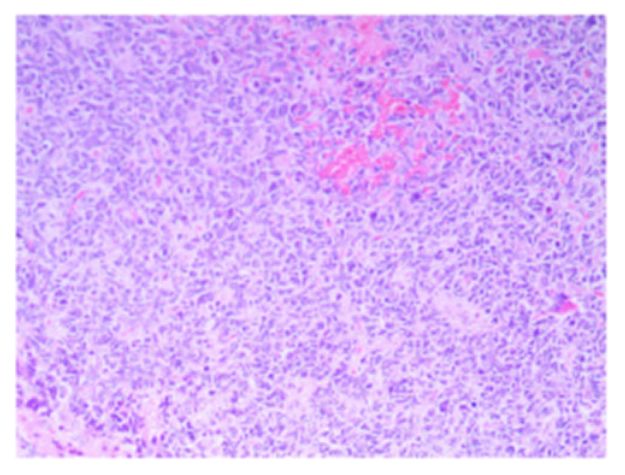

常规病理结果为右侧小脑恶性肿瘤伴坏死,结合免疫组化,考虑成人型髓母细胞瘤(图7)。免疫组化结果:CK(AE1/AE3)-,Vimentin – ,CD99 - ,NSE +,Syn 部分+,CgA -,C···D56 +,TTF-1 -,Ki-67 60%+,GFAP +,CD34 -,CD31 -,S-100 -,Bcl-2 -,Calcitonin -。

图7. 病理结果为右侧小脑恶性肿瘤伴坏死,结合免疫组化,考虑成人型髓母细胞瘤。